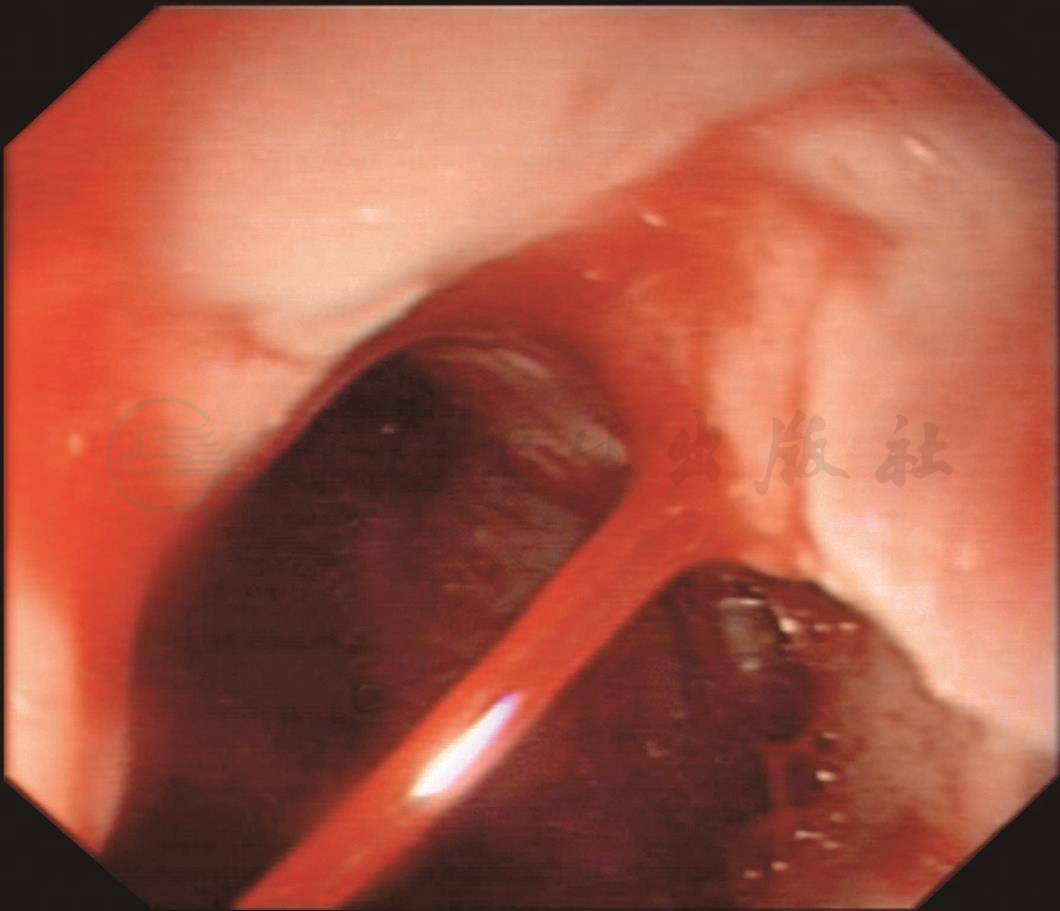

紧急输血、补液、抑酸治疗的同时行急诊胃镜检查,发现食管静脉曲张,贲门处曲张静脉破裂呈喷射状出血。于出血点远端注射组织胶后出血停止,继续连续套扎食管曲张静脉6环(图1),术后患者未再呕血,生命体征平稳,择期行序贯治疗。

A.贲门处曲张静脉喷射状出血

B.注射组织胶后出血停止

C.食管曲张静脉

D.COOK套扎器连续套扎

图1 内镜图片